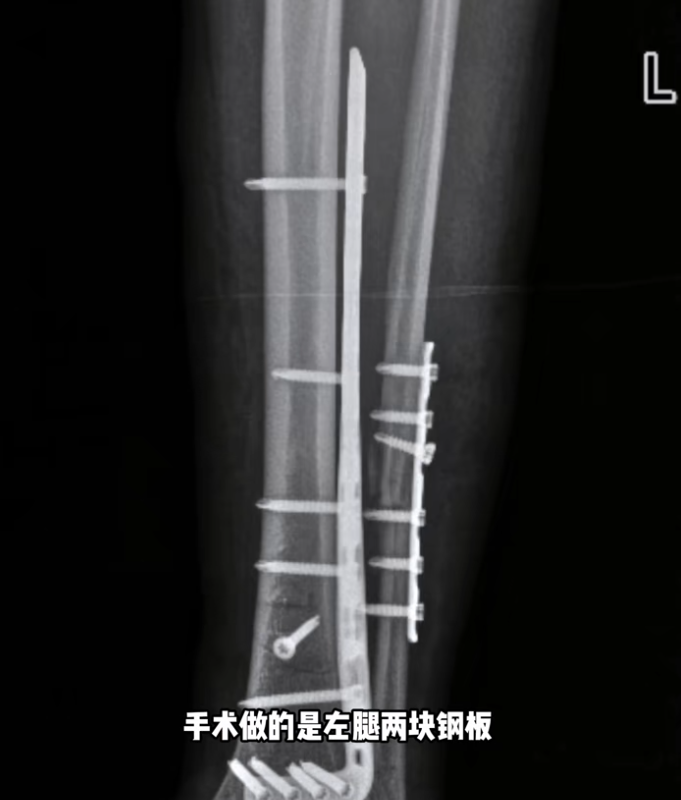

据她2月27日发布的动态,她在新疆滑雪时摔倒,断了4根骨头,右腿胫骨粉碎性骨折,处理伤口的时候,她痛苦喊叫声响彻诊室。

据她描述,轻微的活动都能感受到碎骨扎进肉里,不敢想象有多疼。千一称在新疆接受手术,左腿2块钢板16颗钉子,右腿2条髓内钉和6颗固定钉子,缝了45针。麻醉药效过去后,剧痛和反复发烧都在折磨她,甚至开始说胡话、记忆混乱的症状。3月8日,她发文报平安,称自己状态好多了,并在视频中表示,明年再战。网友们纷纷提醒,如此严重的伤势,不能马上从事剧烈运动的。小丽星骑不快的鸡腿儿:但愿这个不是剧本,这个踝关节面估计已经创伤性关节炎了,手术做完只是开始,后面的康复和后遗症会终生痛苦。量体裁衣:你开心的日子就是这几天,以后康复后遗症有你哭的,我就是一个小骨折康复以后都有一点轻微后遗症。Sophia:明年也战不了,拆钢板还得养一年。我就是,两年没滑雪了,甚至跑步医生都不让。